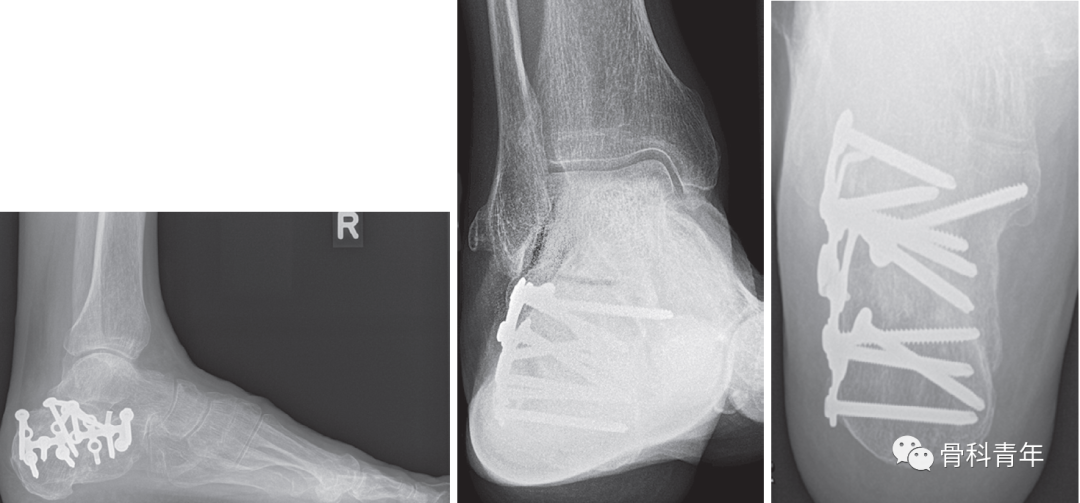

图:跟骨骨折,后关节面塌陷。

对跟骨骨折的手术治疗,外侧“L”形扩大入路切开复位钢板内固定仍是常用的手术方法,本文介绍外侧扩大入路的具体步骤。